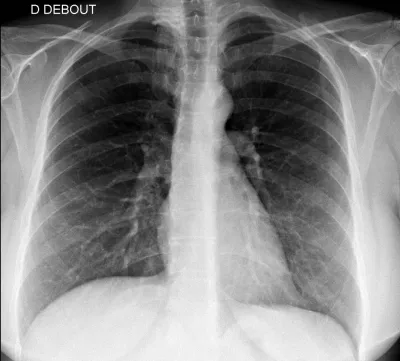

Faire une radiographie du thorax à Marseille et Fuveau

La radiographie du thorax est un examen réalisé couramment dans les centres d'imagerie médicale comme ceux de Marseille Lodi, La Rose et Fuveau, pour la visualisation des poumons mais également de la silhouette cardiaque et des plèvres. Les poumons normaux sont constituée majoritairement d'air et ...